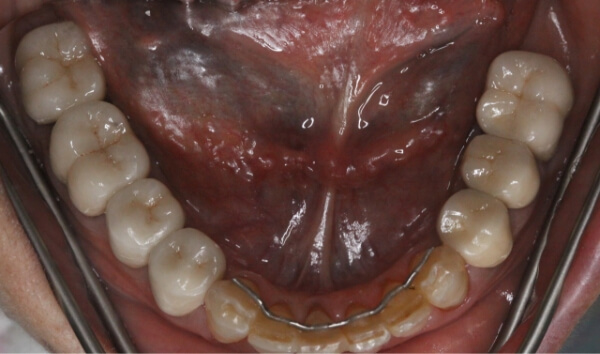

終期

約6ケ月間ブラケットを装着し、歯の隙間がほとんどなくなりました。

患者様も、たった6ケ月で「すきっ歯」が解消されたことにとても感動されており、心置き無く笑顔に慣れると喜んでいました。